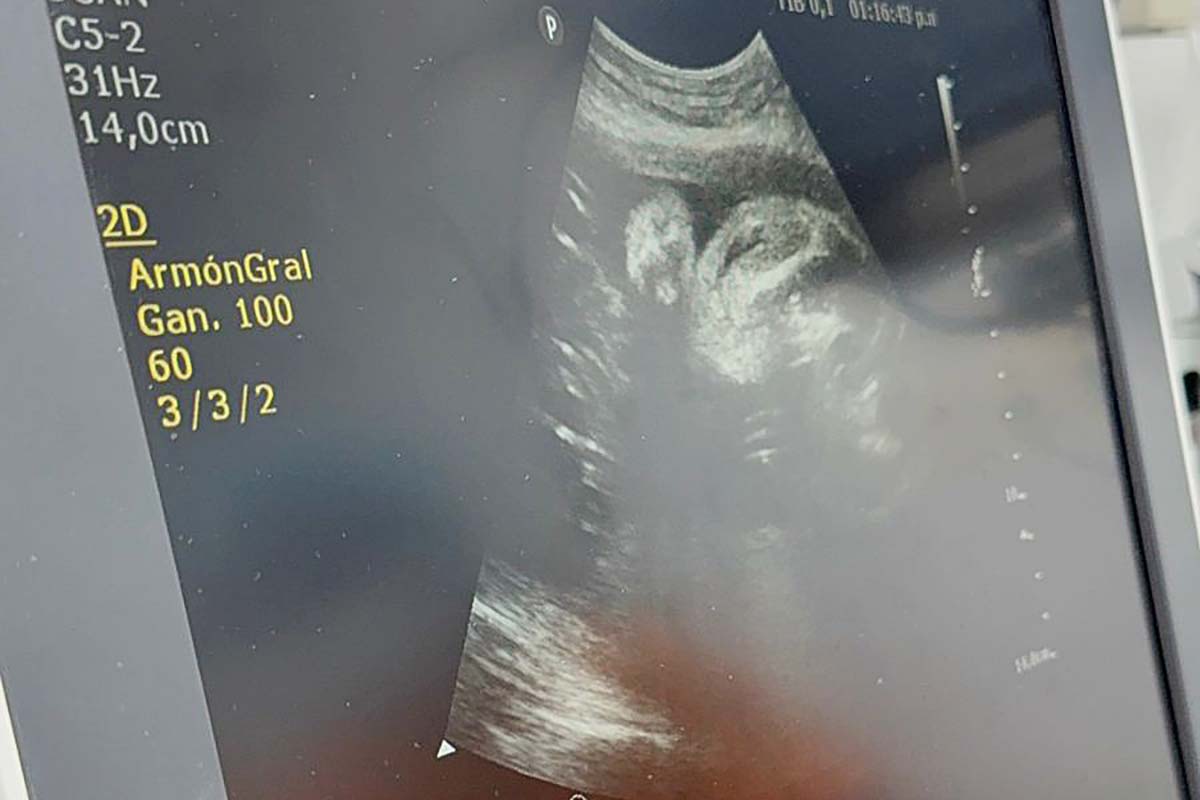

Al respecto, el doctor Guillermo Wilson Ravenau, jefe del servicio de Ecografía de la Maternidad indicó: “Son procedimientos que se hacen en pocos lugares del país, como Córdoba, Buenos Aires y Tucumán. Lo hacemos específicamente en pacientes RH negativo y que han desarrollado un anticuerpo contra un factor positivo. Por ejemplo, en este caso, sería de la embarazada, el feto es positivo, entonces ella desarrolla un anticuerpo contra ese factor positivo. Le produce una anemia porque va destruyendo los glóbulos rojos positivos. Justamente entonces, lo que hay que hacer es reponer la sangre para revertir la enfermedad que puede llegar a ser muy grave. Se produce generalmente en la segunda gestación, no en la primera, es altamente letal y solamente cabe una zona terapéutica que es la transfusión fetal intraútero”.

En tanto, el profesional explicó: “Hemos transfundido al niño, para sacarlo del pozo anémico en el que estaba. Tuvimos que hacer un par de procedimientos y está pendiente un tercero, para poder abatir la situación. El procedimiento es simple y complejo a la vez. La parte simple es la función, me guío, pulso, canalizo el cordón umbilical. Y la parte más complicada es todo lo que viene después, porque aquí se involucra no solo el servicio de Ecografía, sino por ejemplo el de Hematología, que preparan la sangre”.

“La verdad que el paciente ha mejorado muchísimo y ahora estamos pendientes de si hacemos una tercera o lo sacamos. Cabe aclarar, que este tratamiento no es curativo, es paliativo para hacer que el niño nazca y le dé la oportunidad al servicio de neonatología a trabajar su bebé, porque después sigue la segunda fase postnatal. Tienen que examinarlo, cambiar la sangre. Comenzamos en la semana 28 y estamos pendientes del resultado de cómo será la ecografía ahora, y decidiremos si se requiere hacer otro tratamiento o el que seguirá post-natal”, manifestó.

El doctor Guillermo Wilson Ravenau destacó: “Este procedimiento lo realizamos en este embarazo, un poquito grande, porque estaba hidrópico o edematoso, por lo que queríamos quitarle el edema, para que el manejo posterior neonatal sea más sencillo. Claro, que el edema generalizado, que se llama Hidrox, tiene una letalidad importante en los primeros días postnatales. Entonces, la idea es sacarlo de ese problema y dejarlo en mejores condiciones para que el neonatólogo trabaje más tranquilo, no tan presionado. Habitualmente, lo hacemos en edades gestacionales más tempranas, con 22 a 25 semanas de gestación. Pero bueno, esta paciente apareció recién a esta altura del embarazo y con esta situación, que ha sido bastante angustiante, ya muy avanzado todo el proceso, pero lo pudimos revertir, gracias al apoyo del jefe del servicio de Medicina Fetal, doctor Juan Sebastián Pappalardo, que me ayudó en el procedimiento; los servicios de hematología, de anestesia y los residentes, que fueron fundamentales y tienen un peso muy importante en el procedimiento”.